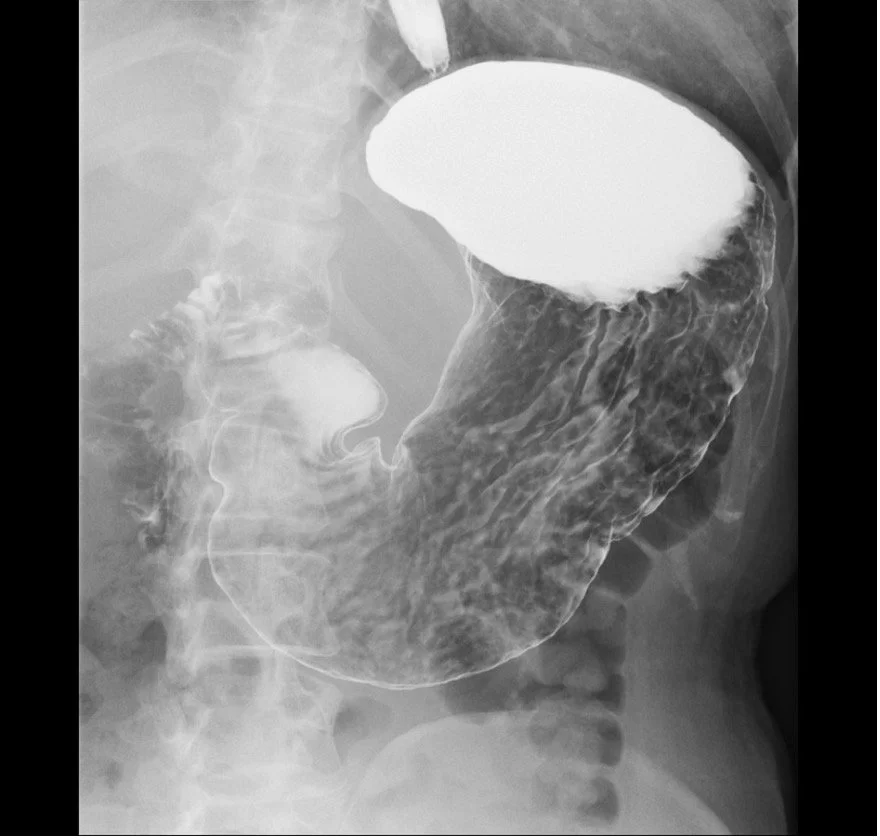

胃X線(バリウム)検査

造影剤(バリウム)を飲んで、胃の形や粘膜の凸凹を見る検査です。バリウムと発泡剤という胃をふくらませる薬を飲んでいただき、検査台の上で体位変換しながら多方向からレントゲン撮影を行います。撮影後、下剤を飲む必要があります。